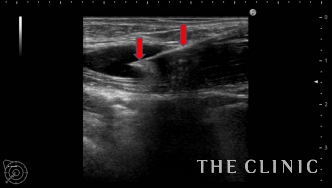

画像は、しこりの中に注射針を穿刺したところと、ヒアルロニダーゼを注入しているところです。

ヒアルロニダーゼが入ると加水分解して白く点状の画像として描出されます。

しこり全体にヒアルロニダーゼが浸透するように十分な量を注入することがポイントです。